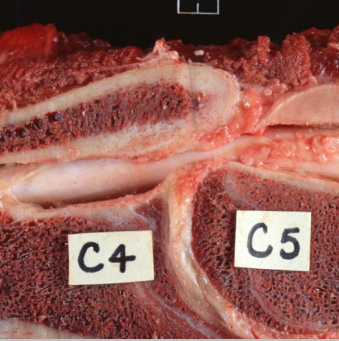

What condition has this horse got?

Cervical vertebral stenotic myelopathy